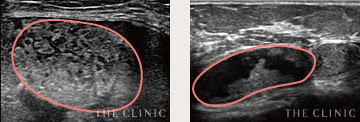

しこりの状態をチェック

オイルシスト

しこり内部の壊死した脂肪がオイル状になっているしこりは、エコーで黒く映し出されます。

充実性

オイル状ではなく脂肪組織が残っているしこりでは、しこりの内部が白っぽく映し出されます。

石灰化

被膜にカルシウムの結晶が沈着したしこりはエコーで投影できず、深部が黒く映ります。

瘢 痕

しこりから壊死脂肪が漏れて炎症すると、しこりが瘢痕化。エコー鑑別が難しい症例です。